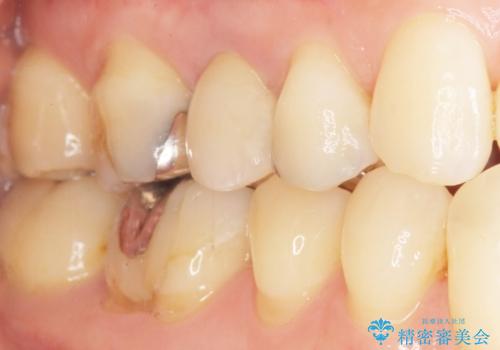

自然な見た目と咬み心地にご満足頂けました。

オフィスホワイトニングを行い、白くなった天然歯に合わせたシェード(お色味)でクラウンを作製しました。

モチベーションが上がり、他の銀歯もセラミックで治していきたいとご希望され、現在治療中です。

クラウンの種類:オールセラミッククラウン スタンダード